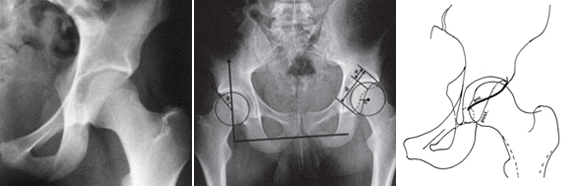

A osteotomia intertrocantérica rotacional é feita de forma a colocar a região necrótica da cabeça femoral fora da área de suporte de carga.

Os resultados são menos bem sucedidos se as lesões necróticas forem de tamanho superior a 50% da cabeça femoral ou se houver um colapso da cartilagem de mais de 2 mm.

O enxerto ósseo vascularizado proporciona um suporte estruturado viável (perónio vascularizado, enxerto vascularizado da crista ilíaca) para prevenir o colapso da cartilagem.

Por causa da irrigação sanguínea e potencial poder osteogénico, o enxerto vascularizado leva à recuperação da área de osso necrótico.